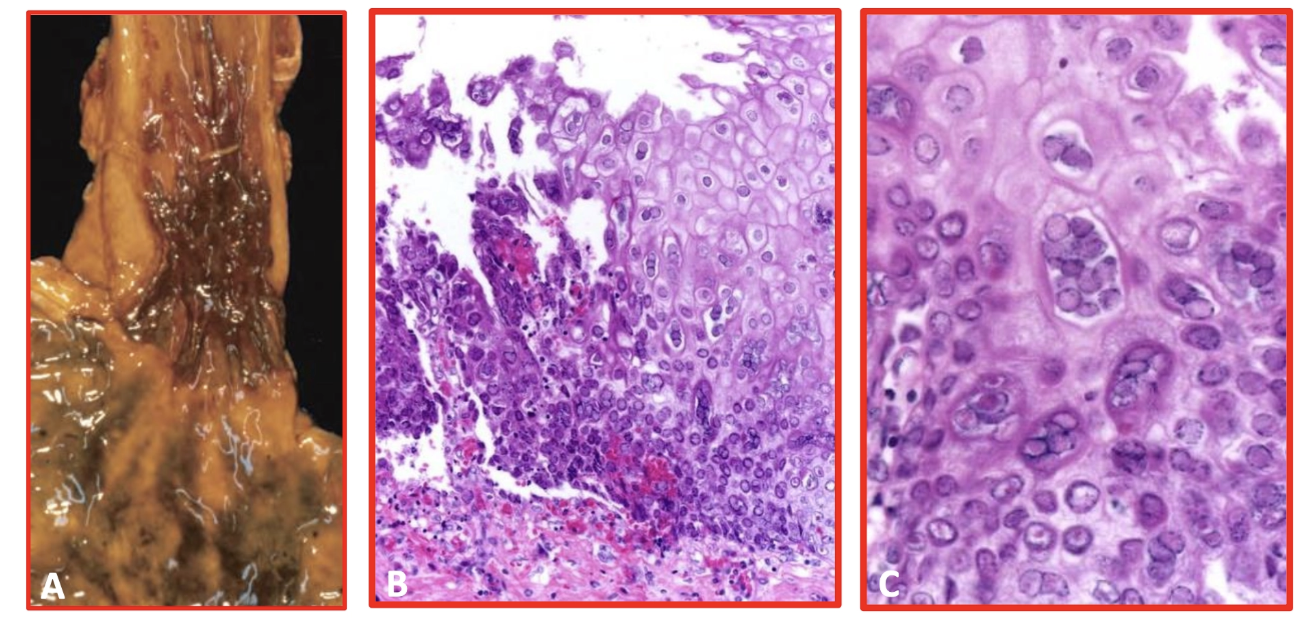

ESÓFAGO DE BARRETT

ESÓFAGO DE BARRETT micro